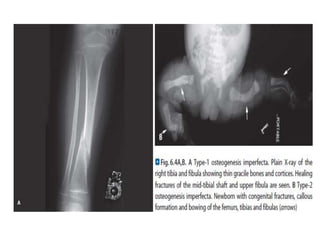

Radiographic features

Radiographic features vary according to the type

of disease and its severity and include

osteopenia and fractures, which may heal with

florid callus formation, mimicking

osteosarcoma.

Bones are thin and under-tubulated (gracile),

normal in length or shortened, thickened and

deformed by multiple fractures.

Intra-sutural (Wormian) bones can be identified

on skull radiographs.

A mild form of this condition (occurs in 70% cases).

It has autosomal dominance inheritance.

Sclera becomes blue.

Bone fragility mild.

Fracture rates in childhood diminish with increasing

skeletal maturity only to increase again in middle life,

particularly in postmenopausal women

Stature is normal or only mildly reduced.

Deafness occurs in adult life.

People suffering from it can expect to live as long as

any normal individual.

Osteoporosis occurs with cortical thinning with

bowed thin gracile long bones.

In 10% fractures are seen at birth.

Most fracture occurs in young children.

Wormian bones are seen in skull.

OI Diagnosis-Plane radiography

32

Obtain a radiographic skeletal survey after birth.

Generalized osteoporosis is present

In milder forms (Types I & IV)–Thin and gracile bones

with thin cortices. Skull vault may be normal.

In the more severe forms (types 2 and 3)-The bones

are thick and short with multiple fractures and

hyperplastic callus formation.

The skull is osteopenic and multiple wormian bones

are present. Multiple rib fractures may cause the bones

to become broad and deformed.

Platyspondyly and scoliosis are often present